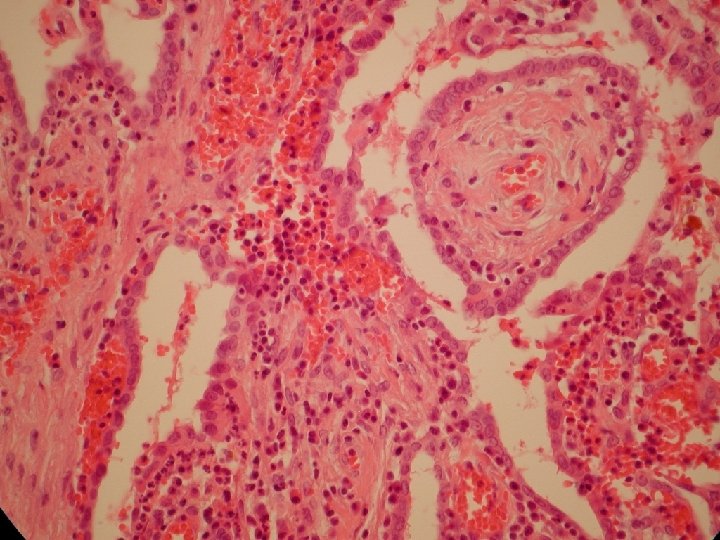

Mikroskopický obraz

Adenomatoidný tumor vajcovodu